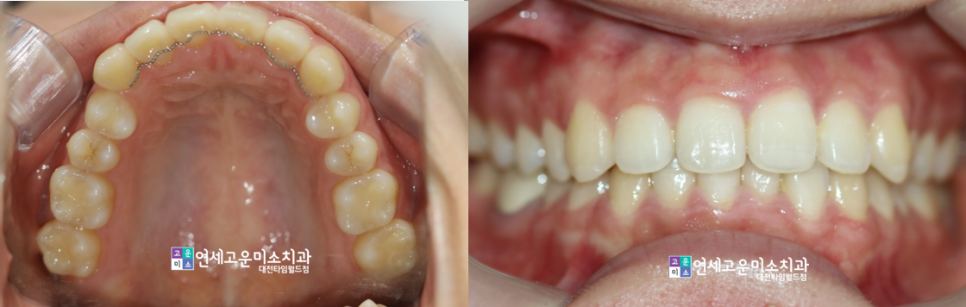

case1-2) 앞니가 삐뚤어요

위에 환자분과 비슷한 케이스고

부분교정으로 훌륭히 마무리가 되었습니다

보통 부분교정의 경우 기간이

6개월에서 1년 정도 소요됩니다.